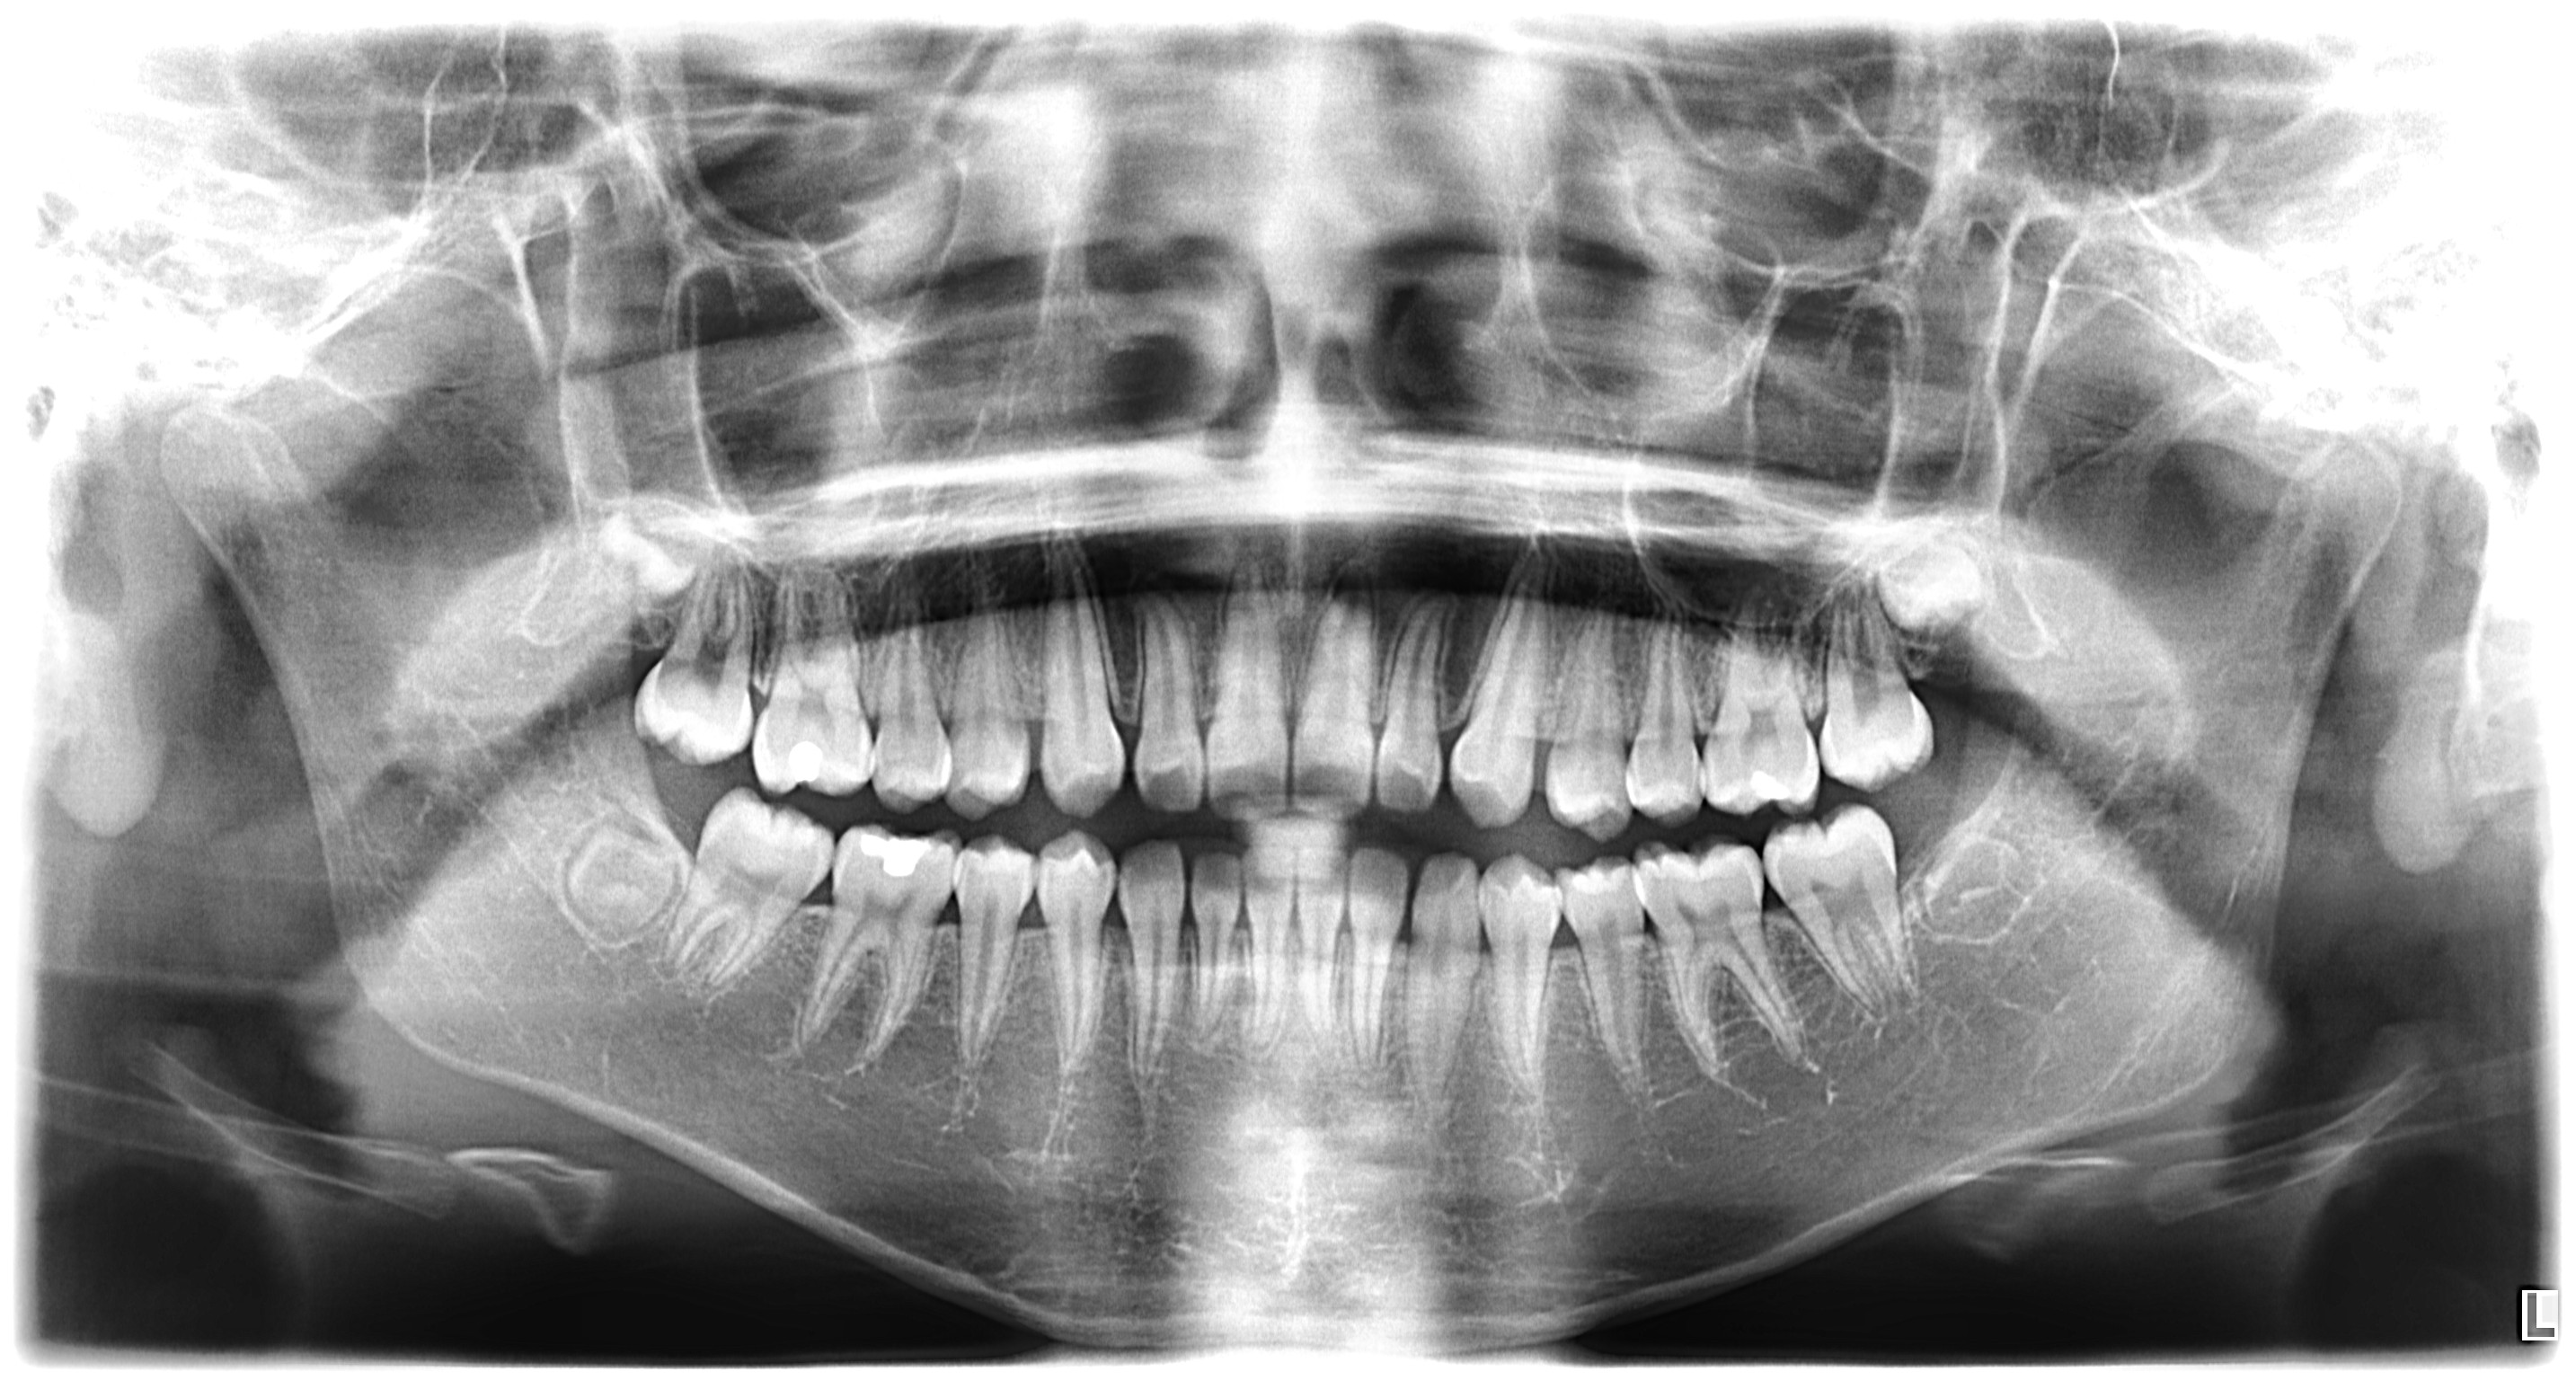

Panoramic X-Ray

A panoramic x-ray captures the entire mouth in a single image, including all teeth, upper and lower jaws, and surrounding structures. This wide-angle view is essential for evaluating overall dental health, jaw disorders, and planning treatments such as implants, braces, and extractions.

Common Uses:

• Full mouth assessment

• Implant planning

• Orthodontic evaluation

• Jaw disorder diagnosis

Example Image:

Panoramic X-Ray example 1